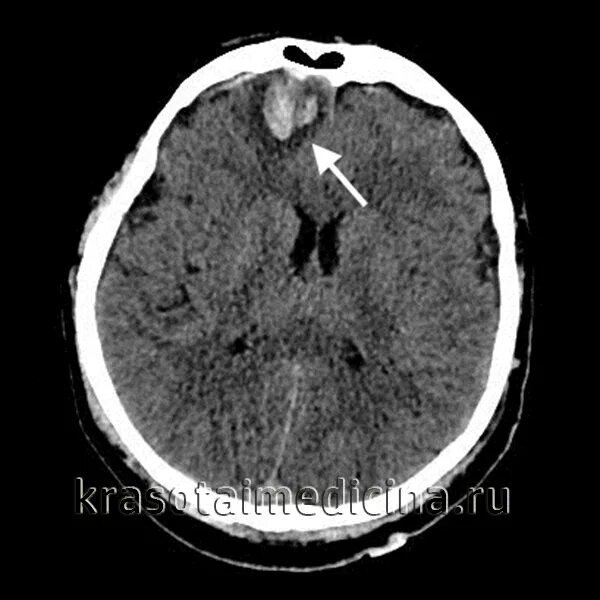

Ушиб головного мозга кт